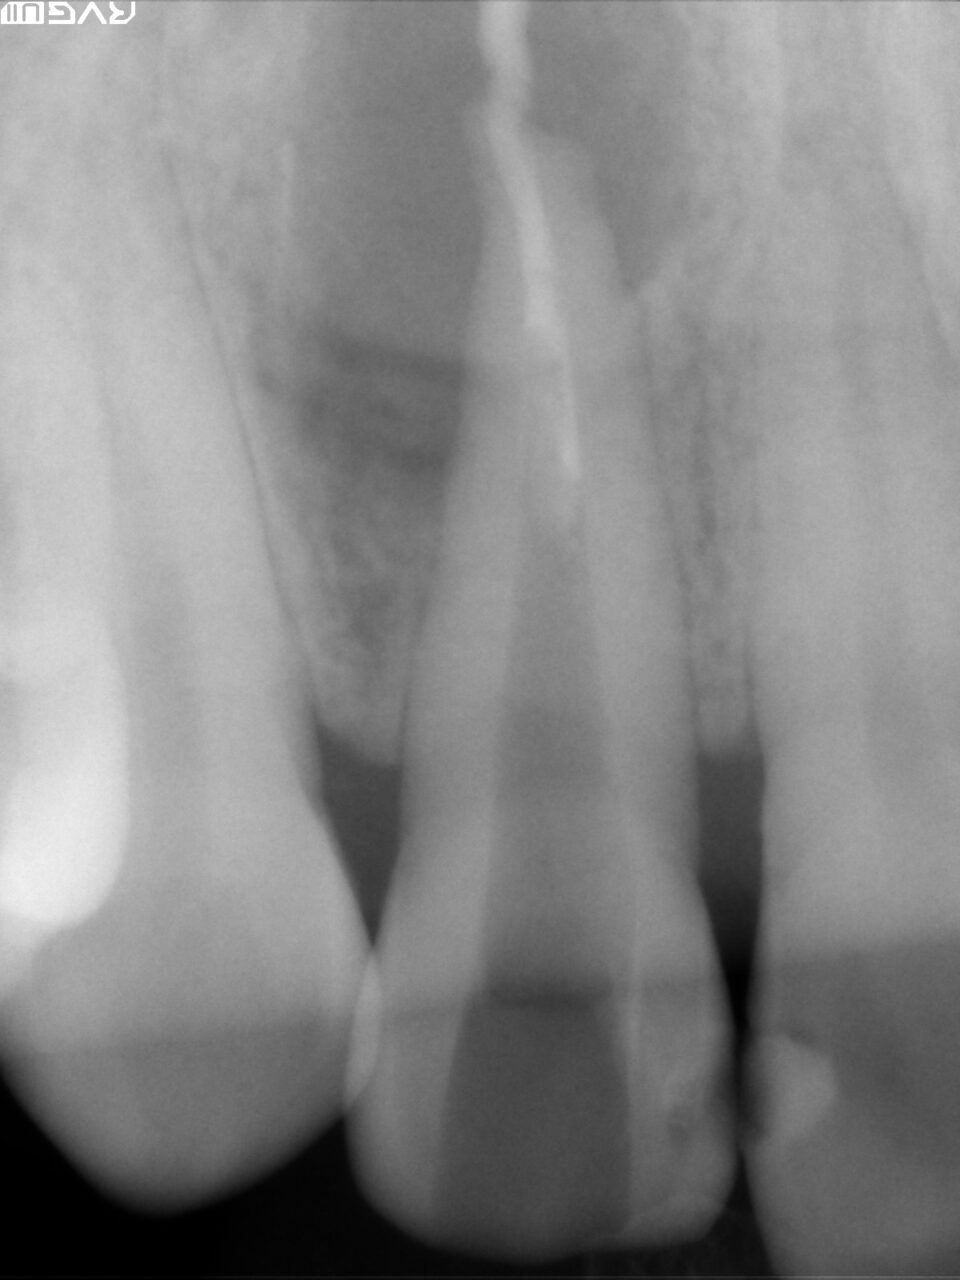

根尖までの長さや根尖孔の太さを確認するためにファイルを入れてレントゲン撮影を行います。

根管形成が終わり、根管洗浄を十分に行い、バイオセラミックによる根管充填を行ないました。

根尖部よりバイオセラミックが出ているが、臨床的には何も問題はありません。この語、骨が再生されるまでには数ヶ月時間かかります。